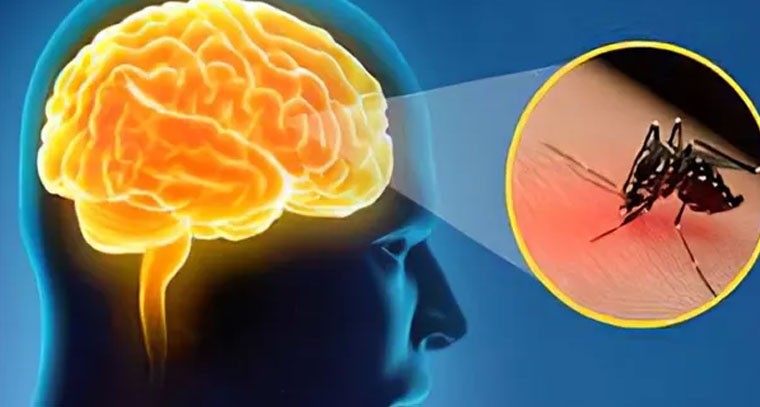

మరో కొత్త వైరస్ కలకలం.. మెదడుకి జ్వరం.. ఆపై మరణం

Publish : Sun, Dec 01, 2024, 06:32 PM